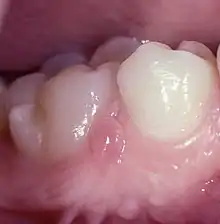

The lesions are bilaterally situated in the attached gingiva or close to the border of the mucosa lingual to the two mandibular canines (Fig.1).[6]

Fig.1.Retrucuspid papillae lingual to both lower canines.

However, they could in a few individuals also be seen simultaneously in the molar region and on the lingual side (Fig.2).[7] They were 2–3 mm wide and high and covered with normal mucosa. Their tips were erected or could be folded down, mimicking the entrance of a periodontal abscess, but no duct was present.

Fig.2. Retrocuspid papilla in molar region labial gingiva mimicking a periodontal abscess